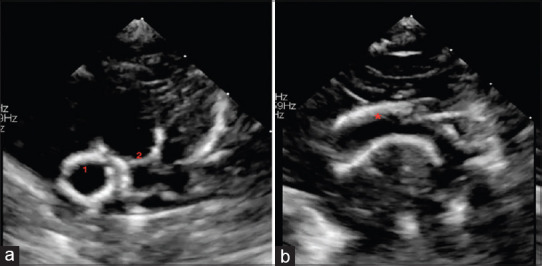

Generalized arterial calcification of infancy is a rare entity with poor fetal and postnatal outcomes and high morbidity in survivors. Half of the cases are diagnosed intrauterine due to hemodynamic compromise, and the associated manifestations pose unique management challenges. We hereby report an account of a fetal diagnosis in a referral for hydrops with postnatal evaluation and management.